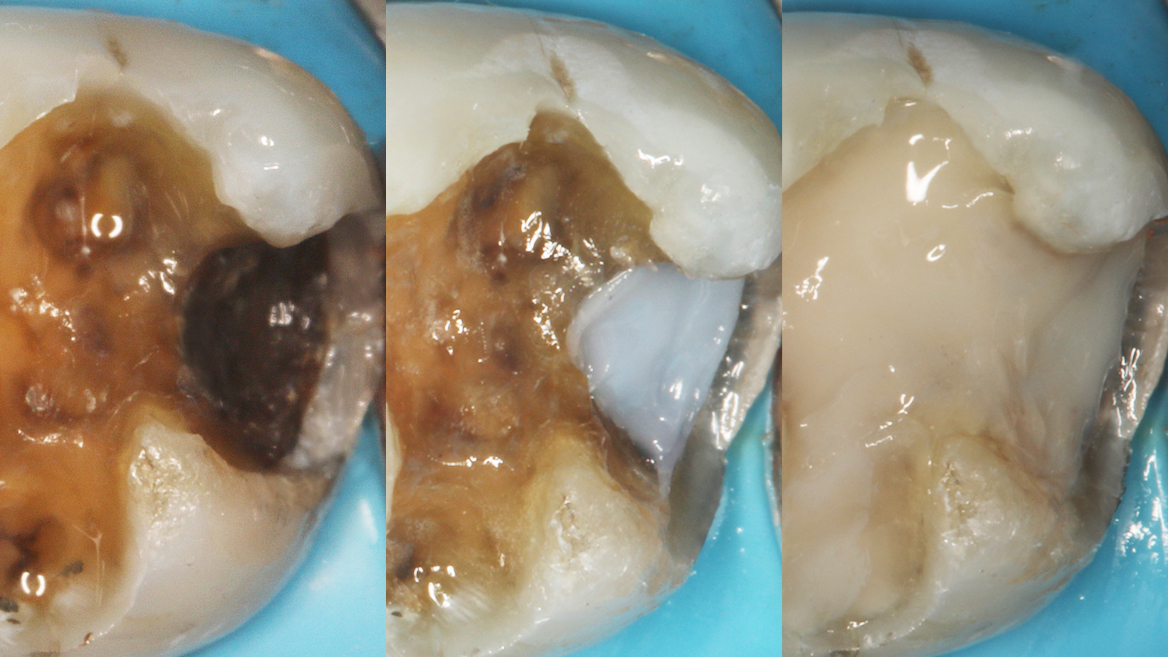

Every day, dentists manage challenging cases with the help of Charisma Diamond & Topaz ONE Shades. Check out what your colleagues say about the product and see the broad variety of cases already done by them!

ONE shade cases – great results around the world

Before & After Cases

“The class II filling was completed in 24 minutes.”

Prof. Nicola Scotti, University of Turin, Italy